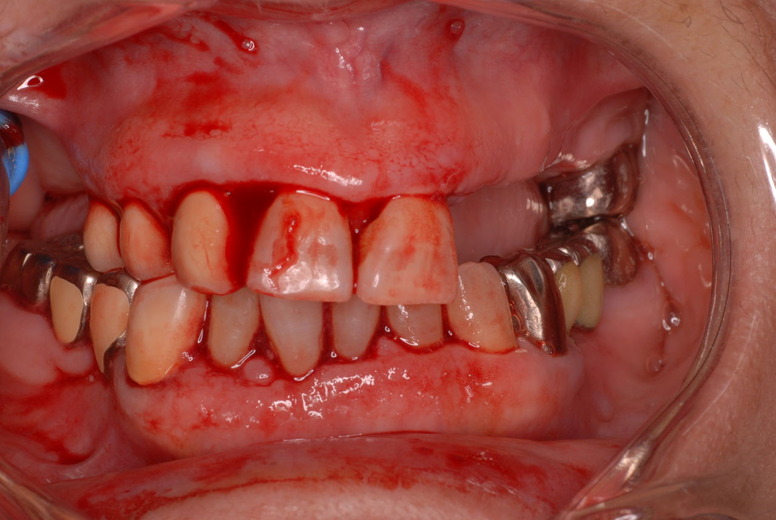

入れ歯の話から入りました。色々不満で注文があるようです。でも話が一段落して口腔内を調べると殆どの歯が重症で抜けそうな歯だらけなのです。

ご自分でやられても歯茎から血が出ないと話をされていましたが、私がブラシを当てると悲惨な状態であることがわかりました。